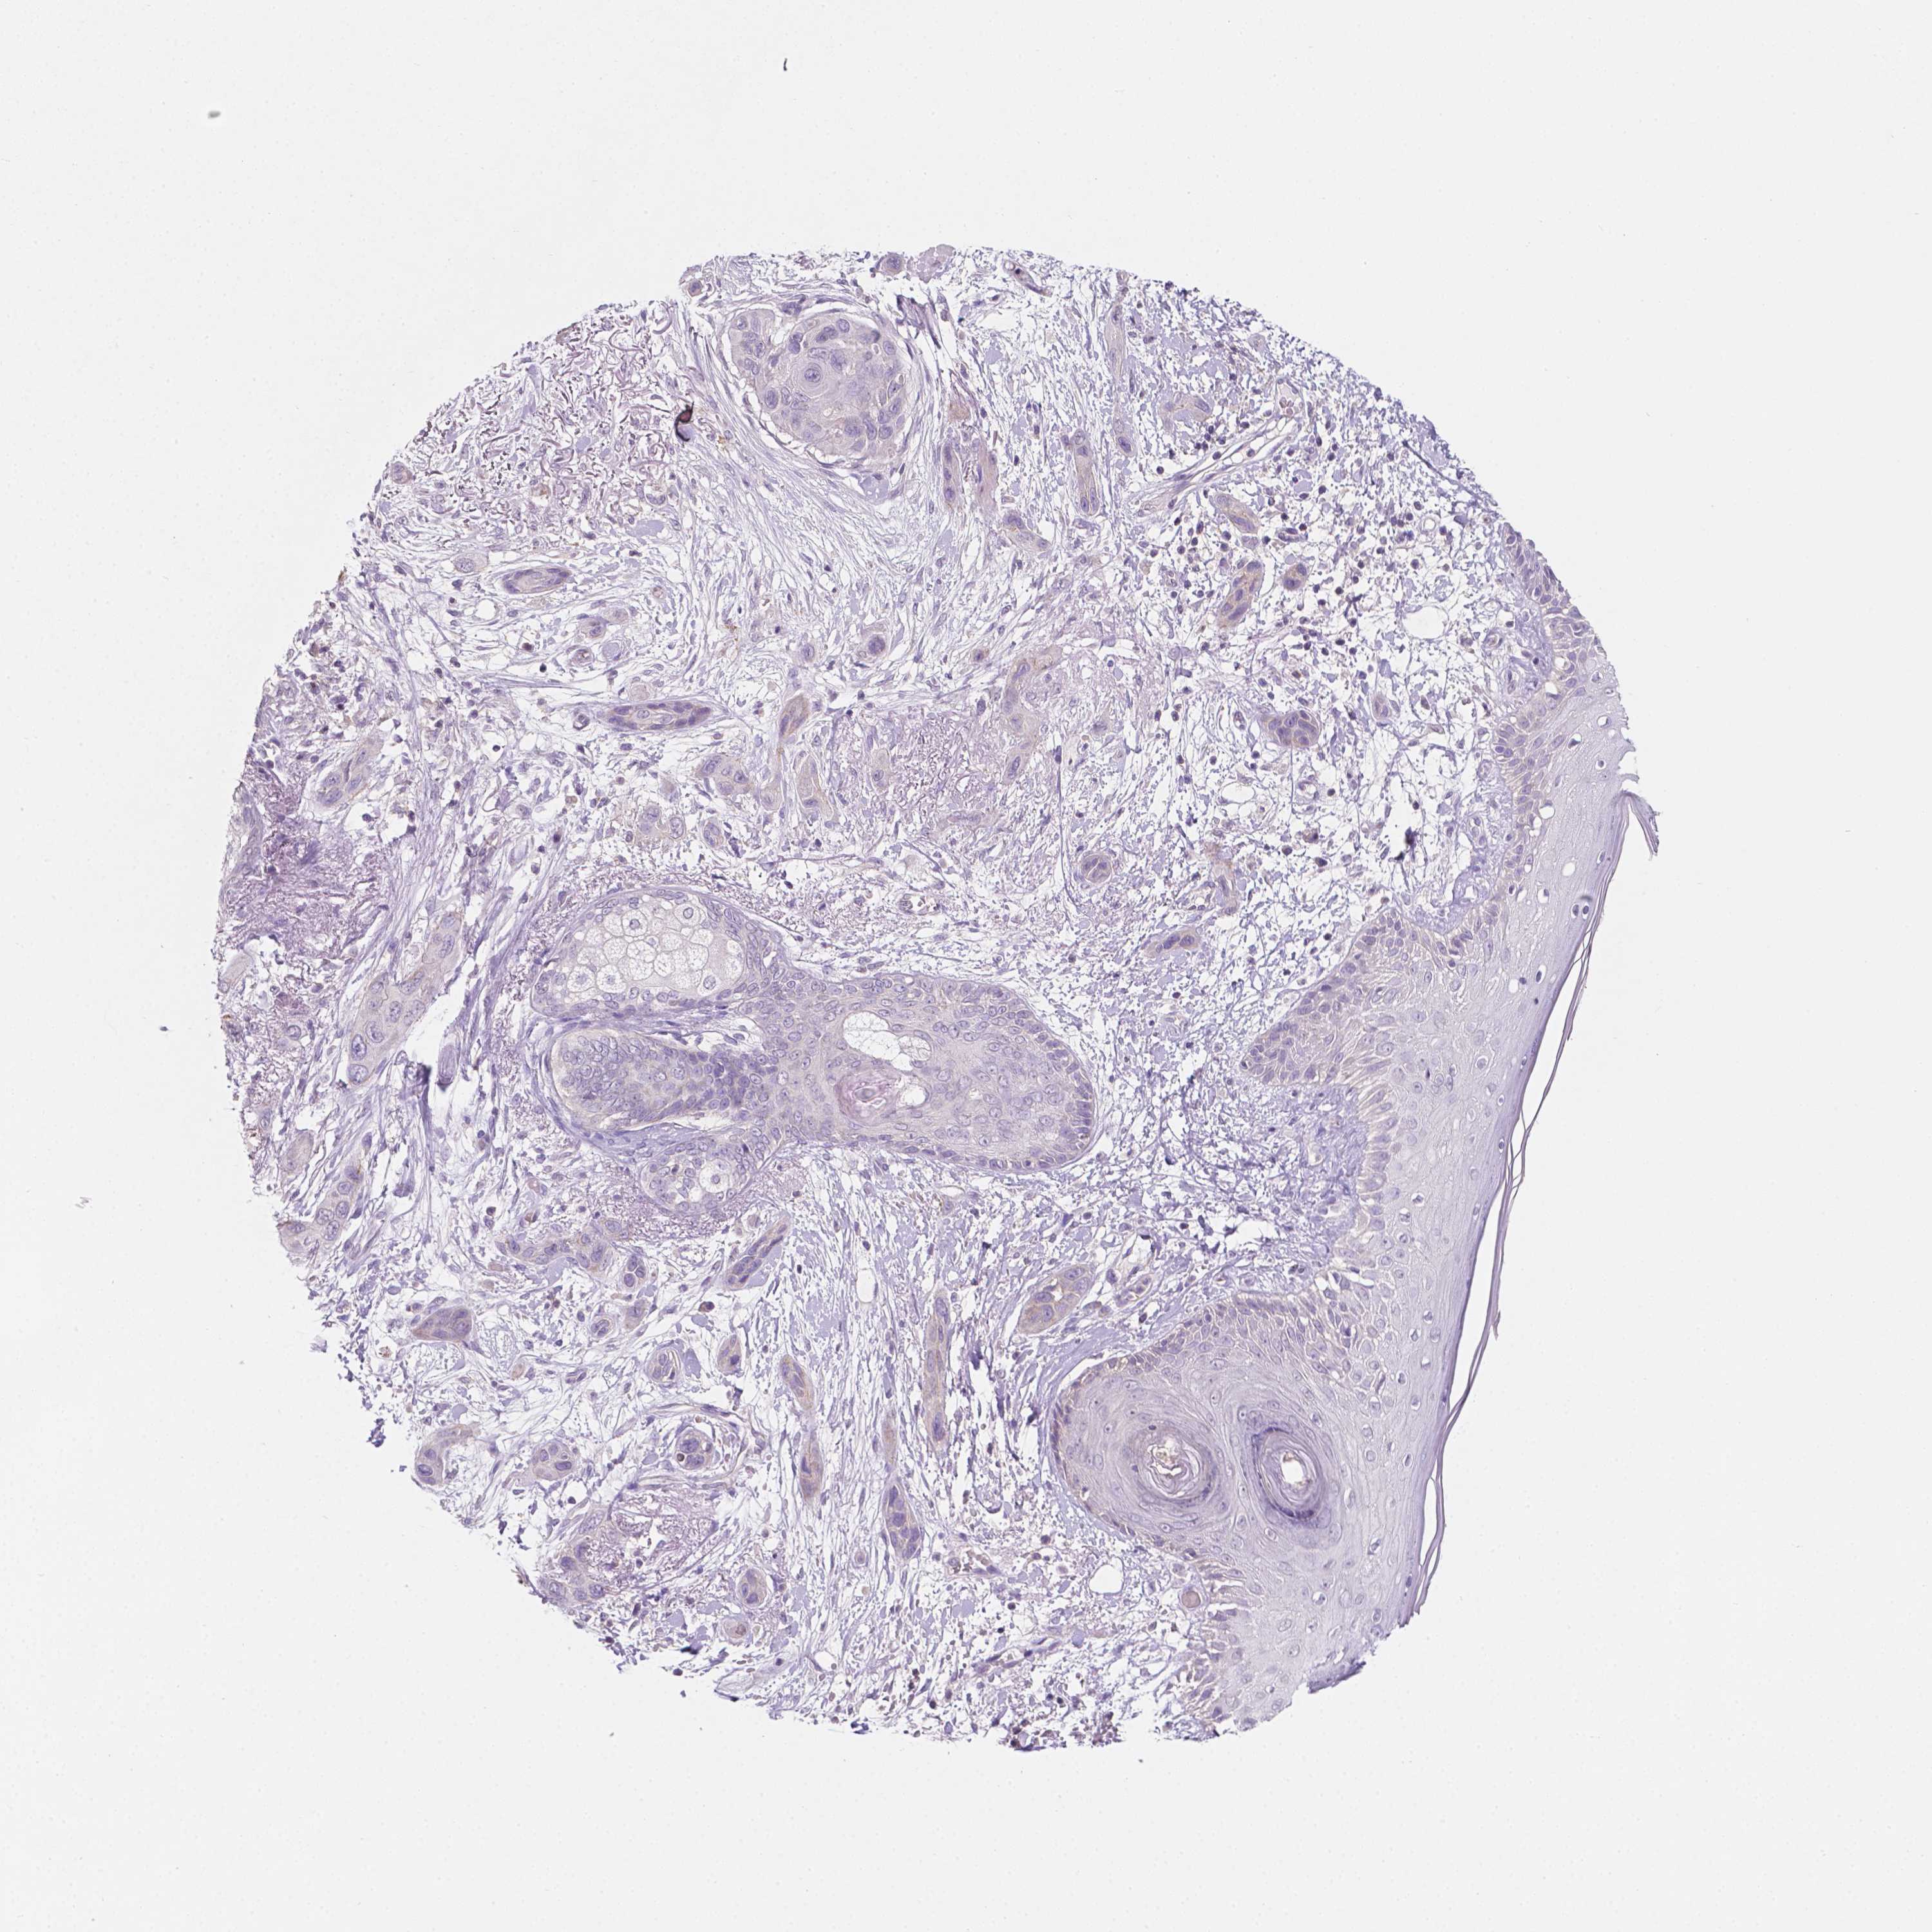

SKIN CANCER - Protein expressioni

A mouse-over function shows sample information and annotation data. Click on an image to view it in a full screen mode. Samples can be filtered based on level of antibody staining by selecting one or several of the following categories: high, medium, low and not detected. The assay and annotation is described here.

Antibody stainingi

Antibody staining in the annotated cell types in the current human tissue is reported as not detected, low, medium, or high, based on conventional immunohistochemistry profiling in selected tissues. This score is based on the combination of the staining intensity and fraction of stained cells.

Each image is clickable and will lead to virtual microscopy that enables deeper exploration of all samples and also displays staining intensity scores, fraction scores and subcellular localization as well as patient and tissue information for each sample.

CAB068186

Staining

High

Medium

Low

Not detected

Squamous cell carcinoma, NOS